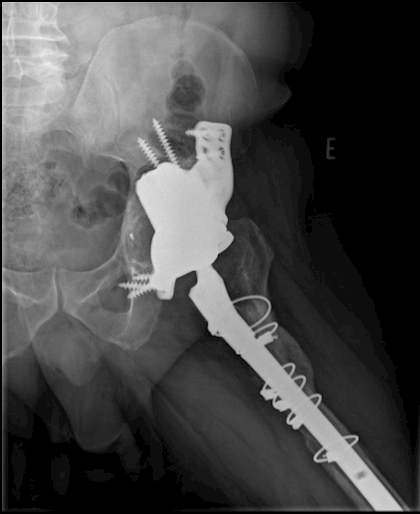

Preoperative: 3D Proposal